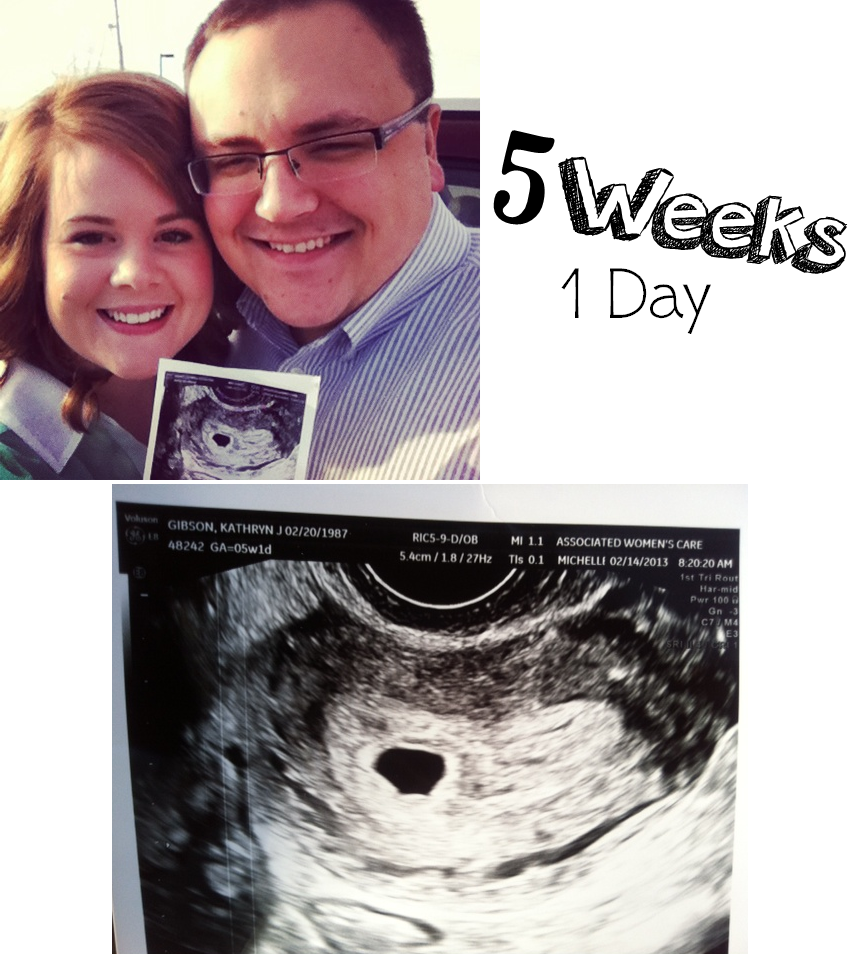

Katie.J.Gibson: 5 Week 1 Day Ultrasound